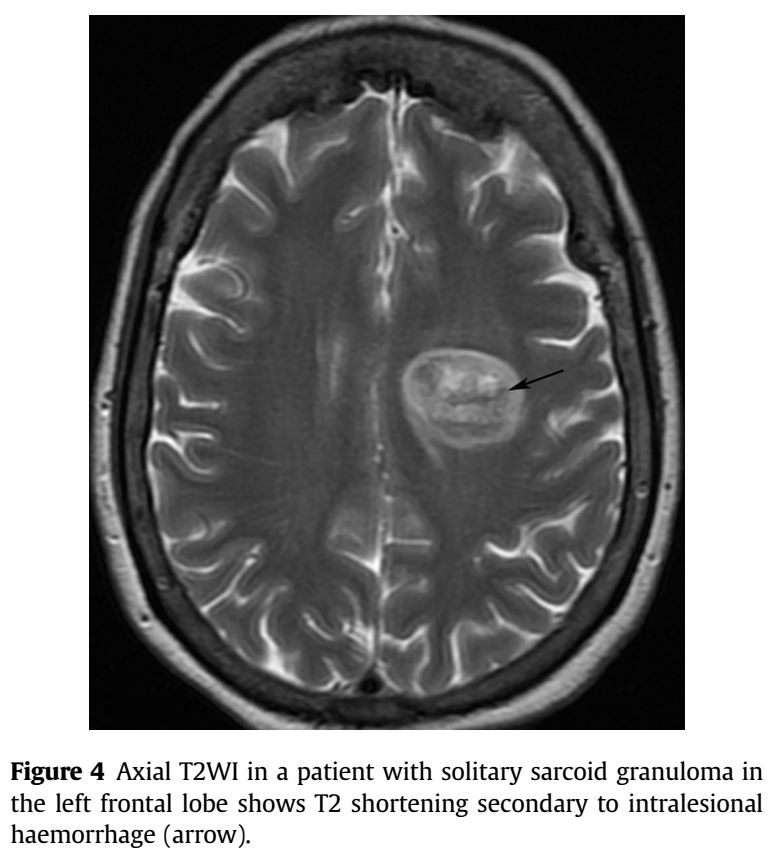

➤表现为出血: